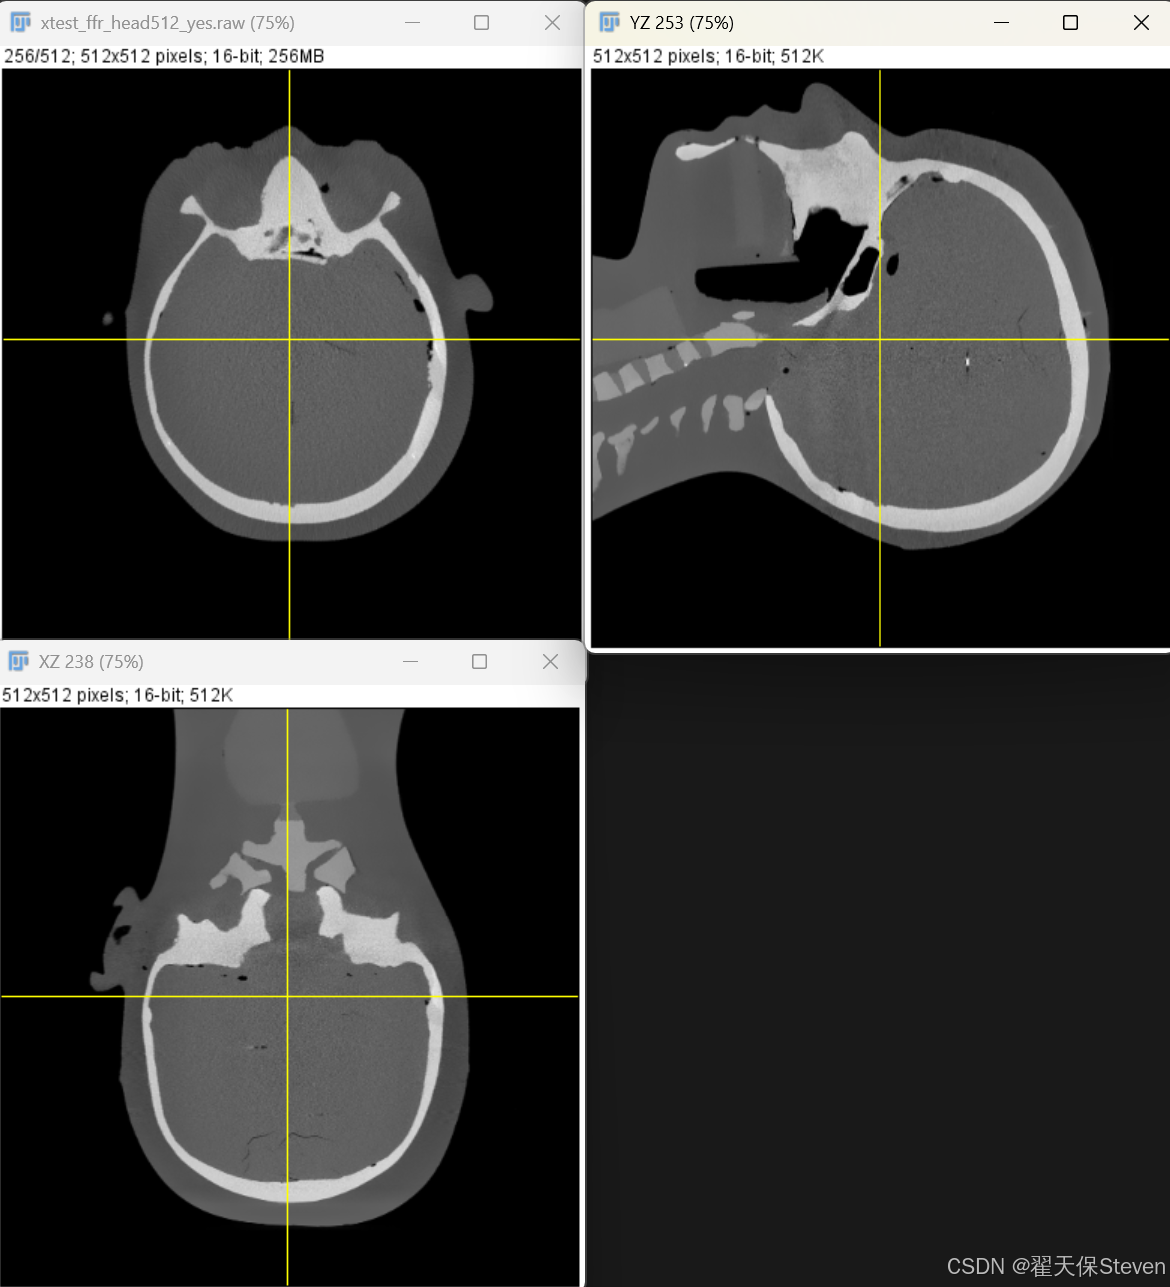

3.5 反投影重建

反投影是将经过加权与滤波处理的投影数据,沿X射线传播的反方向映射到三维重建空间,累加形成物体的三维密度分布。其核心逻辑是:每个重建体素的密度值由所有穿过该体素的X射线对应的滤波后投影数据加权累加得到。

根据FDK算法的核心重建公式,离散化后的反投影计算式为:

其中N为投影角度总数,为角度间隔的等效权重,

为反投影加权因子,用于修正X射线对不同位置重建体素的贡献权重。积分公式里的归一化系数

离散化时被省略,影响不大,因为重建完成后还要进行HU矫正。

反投影过程中,需通过双线性插值计算重建体素在探测器上的对应坐标(a(x,y,β), b(x,y,z,β))处的滤波后投影数据,确保投影信息向三维空间的精确映射。重建后图像三视图如下所示(坐标系为Dicom-HFS体位)。